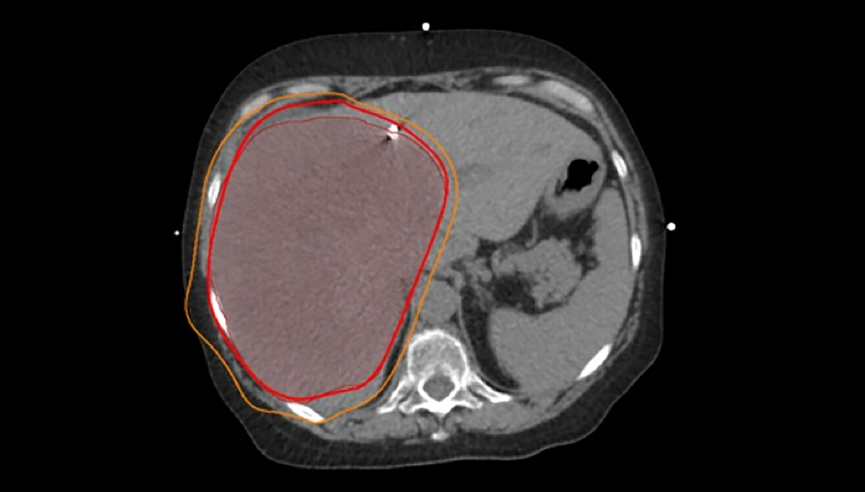

肝内胆管癌(发生在肝脏内部胆管的癌症)中,有一类肿瘤特别棘手,它们体积非常大,甚至超过10厘米。

一方面,要想对这么大的肿瘤产生效果,就必须用很高剂量的放射线,但肝脏本身承受能力有限;另一方面,这些肿瘤往往贴着胃、肠道等重要器官,一旦误伤,后果会很严重。

MD安德森是全美癌症专科排名第一的癌症中心,在这里,医生可以把放射线“雕刻”得非常精准,就像用一束可以拐弯、聚焦的光,既能集中火力打在肿瘤上,又尽量避开周围正常组织。这就让医生有能力把剂量提高到“足以消灭肿瘤”的水平,同时把副作用控制在可接受范围内。